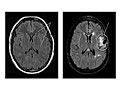

Magnetic resonance imaging (MRI) is a test that uses a magnetic field and pulses of radio wave energy to take pictures of the head. In many cases, MRI gives information that can't be seen on an X-ray, ultrasound, or computed tomography (CT) scan.

For an MRI of the head, you lie with your head inside a special machine (scanner) that has a strong magnet. The MRI can show tissue damage or disease, such as infection or inflammation, or a tumor, stroke, or seizure. Information from an MRI can be saved and stored on a computer for more study. Photographs or films of certain views can also be made.